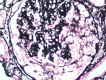

Diabetic kidney disease is a very prevalent complication in the context of type 2 diabetes. However, there is evidence showing a high variability in diagnosis when a kidney biopsy is performed. We present a case of a woman with a diagnosis of diabetic kidney disease, systemic arterial hypertension, obesity, and a high risk of progression of chronic kidney disease who presented with a sudden onset nephrotic syndrome and rapidly progressive deterioration of renal function. Kidney biopsy revealed pauci-immune extracapillary glomerulonephritis with acute thrombotic microangiopathy and class IIa diabetic nephropathy. Antineutrophil cytoplasmic antibodies (ANCA) and low complement were detected. The patient received treatment based on plasma exchanges, steroids with methylprednisolone and prednisone and intravenous cyclophosphamide with improvement of renal function. In conclusion, expansion of kidney biopsy criteria in patients with a diagnosis of type 2 diabetes is mandatory to provide adequate treatment and prognosis in the context of a high prevalence of alternative or concomitant disease.